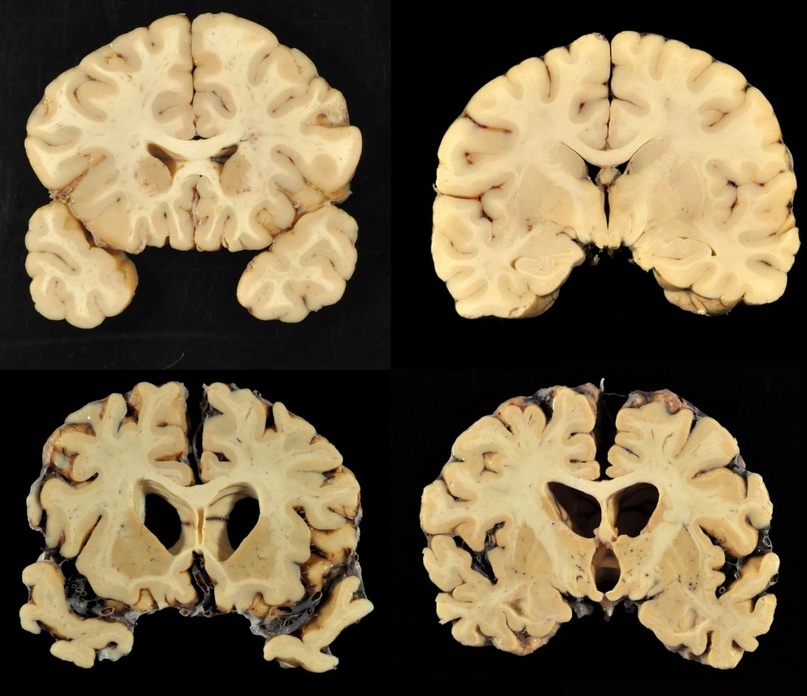

Тем не менее, при большом сходстве патогистологических изменений между болезнями Крейтцфельдта-Якоба, куру и скрепи имеются отличия. Так, амилоидные бляшки при болезни Кройцфельдта-Якоба наблюдаются в 9%, а при куру они встречаются в 70% случаев.

Уже давно было подмечено, что все симптомы при болезни Кройтцфельдта-Якоба подкрепляются патогистологическими изменениями. Так, при изменении моторных нейронов отмечено выпадение многих нервных клеток в двигательной области коры, включая гигантские пирамидные нейроны (клетки Беца), а также демиелинизацию пирамидных путей и утрату клеток передних рогов спинного

болезни Кройтцфельда-Якоба